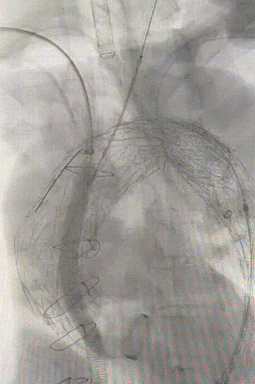

双球囊同时扩充

7. 进行最终造影,支架形态良好,弓上三根分支血管显影通畅,腹主段造影显示内脏区分支显影良好,结束手术。

gore医疗怎么样「胸有乾坤」强弓硬弩 一蹴而就——CTAG弓上三开窗治疗主动脉夹层病例报道_https://www.jmylbn.com_新闻资讯_第16张

主动脉弓最终造影